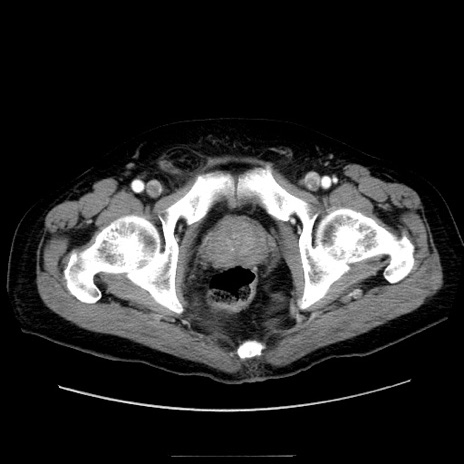

症例30(横断像)

【症例】80歳代男性

【主訴】臍周囲痛

【現病歴】約6時間前から臍下部痛が出現。次第に腹部膨隆・背部痛も生じてきたため来院。背部痛の場所は変化しない。

【身体所見】意識清明、BT 36.3℃、BP  131/87mmHg、P 87bpm、SpO2 100%(RA)、臍周囲自発痛・圧痛あり、反跳痛なし、自発痛部位に一致して板状硬あり、腹部膨隆、腸雑音減弱、CVA tenderness両側陰性。